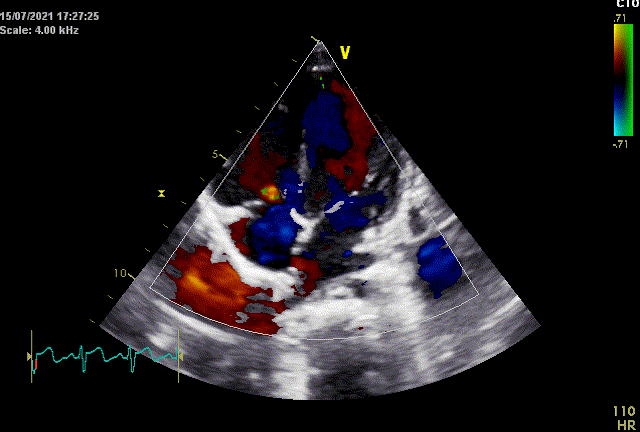

超声心动图是先天性心脏病诊断和随诊的重要检查,正确解读超声心动图报告指导临床实践,是心内科医生必须掌握的基本功。今日话题将聚焦常见先天性心脏病,系统讲解房间隔缺损(ASD)的超声诊断,分享临床诊疗经验。

彩色多普勒血流显像及频谱多普勒:心房水平可探及左向右分流,分流束宽约_mm,各瓣膜血流速度未见增快,三尖瓣见[少]量反流束,估测肺动脉收缩压为_mmHg。

第7条对彩色多普勒血流显像及频谱多普勒的描述。

有几点提示:

心房水平左向右分流是房间隔缺损的表现,如合并肺动脉高压时会表现为双向分流或右向左分流;

ASD主要的超声表现是房间隔连续性中断、心房水平分流以及继发的右心增大和肺动脉压力升高。